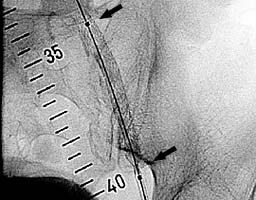

В место стенозов установлен

саморасправляющийся стент (рис.5).

Стенозы устранены (рис.6).

| Рис.5 |

Рис.6 |